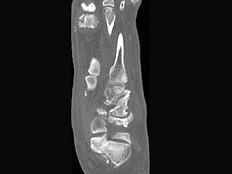

问题 男,56岁,踝关节肿胀,有糖尿病史,结合图像,最可能的诊断是?(?)

选项 A.创伤性关节炎 B.退行性关节病 C.痛风 D.类风湿关节炎 E.神经性关节病

答案 E